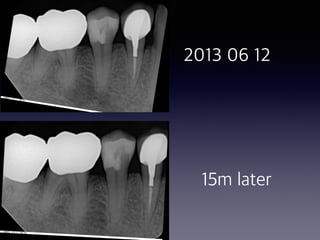

Endodontic sealer

#30

#9, #10

#12,#14

#21

#20 #30

2014 11 10 2014 11 18

2014 11 19 2015 02 26